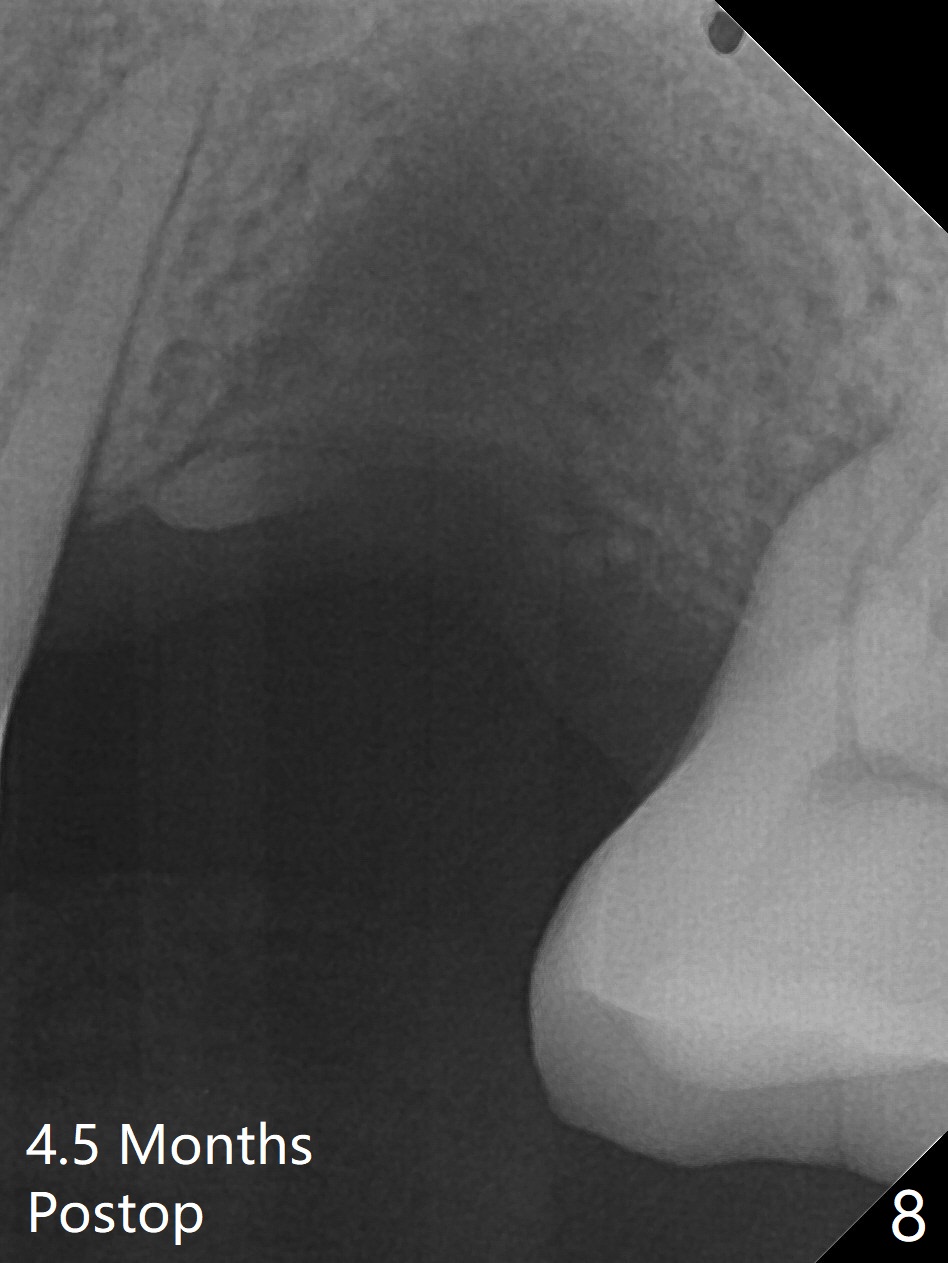

Immediately preop reanalysis of CT shows that there may be palatal thread exposure at #14 when a 4.5x14 mm tissue-level implant is placed equigingival (Fig.1,2). After sinus lift with IS 4x10 mm dummy implant with guide, the tissue-level tap and implant placed free hand look deep (Fig.3,3'). CT reveals possible 3 palatal threads exposed (Fig.4,5 arrowheads), which is associated with change in trajectory due to the palatal shift of the apex of the implant (arrow), as compared to the design of the bone-level implant (Fig.6). When there is a slope in the ridge and/or sinus floor, do not shift implants and use the guide for implant placement. If switching is necessary, use a final drill without underprep (Fig.7 red) through the sinus floor after sinus lift to avoid apical implant deviation. To fix the palatal thread exposure, palatal flap is raised. In fact the implant has to be removed for the incision. When the implant is re-placed deeper by ~ 1mm, there is a thread exposed. Bone graft is placed with collagen membrane. As a 4.5x3 mm abutment is placed, the implant is found to be unstable. Periodontal dressing is applied. In fact the implant exfoliates with the abutment 4.5 months postop (Fig.8). Bone graft seems to be necessary (sticky bone). Tissue level implant should be avoided for patient with poor oral hygiene. Return to Upper Molar Immediate Implant, Trajectory II 3 Xin Wei, DDS, PhD, MS 1st edition 08/30/2019, last revision 05/18/2020